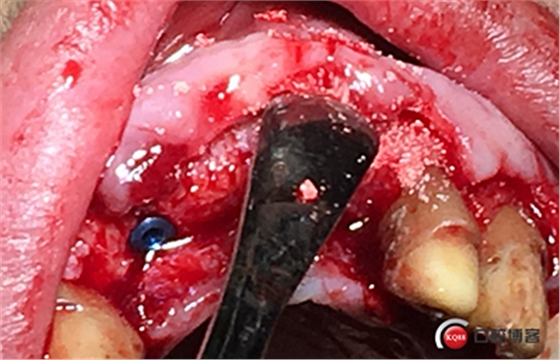

大家注意這個動作,雖然不翻瓣,但要將唇側(cè)倒凹處骨膜剝離。

植入植體。

將骨粉塞入剝離的骨膜下間隙里既唇側(cè)倒凹處,盡量塞滿。